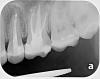

sus Опубликовано 15 октября, 2013 Автор Поделиться Опубликовано 15 октября, 2013 И снова о зубах мужа. Вот серия снимков, сделанная в феврале. Сейчас нам выдали огромный план лечения, правда, он основан в том числе и на визуальном осмотре от сентября, вроде бы видна нехорошая динамика, но снимков не далалось, так что, к сожалению, ничего от сентября приложить не могу. Рекомендации докторов (нумерацию перевела в российскую): Первая очередь: коронки на 15, 36, 37, причем со всеми тремя есть шанс, что придется делать эндо (!)Вторая: коронки на пресловутые 25, 26Третья: пломбы на 17, 16, 24, 27, 34, 35, 45, 46. Понимаю, что без свежих снимков вопрос может быть неуместен, но неужели все так плохо? Особенно по первой очереди срочности - никак пломбами такой объем не сделать? Спасибо большое! Ссылка на комментарий